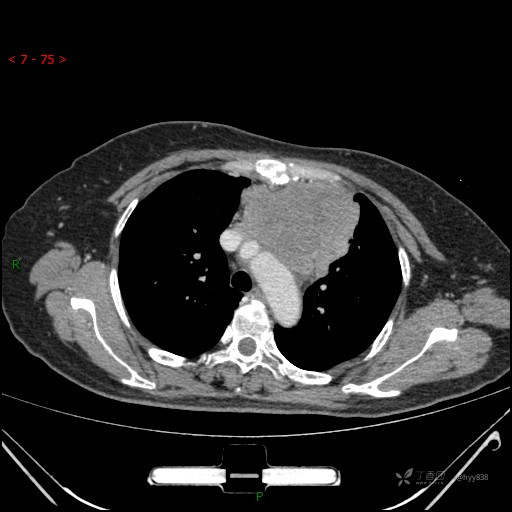

简要病史:患者诉3月余前患新冠肺炎,出现持续性胸闷,活动后可缓解,无胸前区压榨感,无畏寒发热不适,无胸痛咯血、呼吸困难,无恶心、呕吐,无腹痛、腹胀、腹泻等不适,未予以重视,未行特殊处理。患者胸闷持续存在,为进一步诊治,3天前于本院查胸部CT提示前纵膈团块状软组织密度影,肿瘤性病变可能,心包积液,左上肺磨玻璃结节,右下肺增殖灶可能建议进一步检查。门诊以“前纵膈占位” 收入我科。 患者本次起病来精神、食欲、睡眠尚可,大小便正常,体力、体重无明显变化。

辅助检查:CT

静脉期